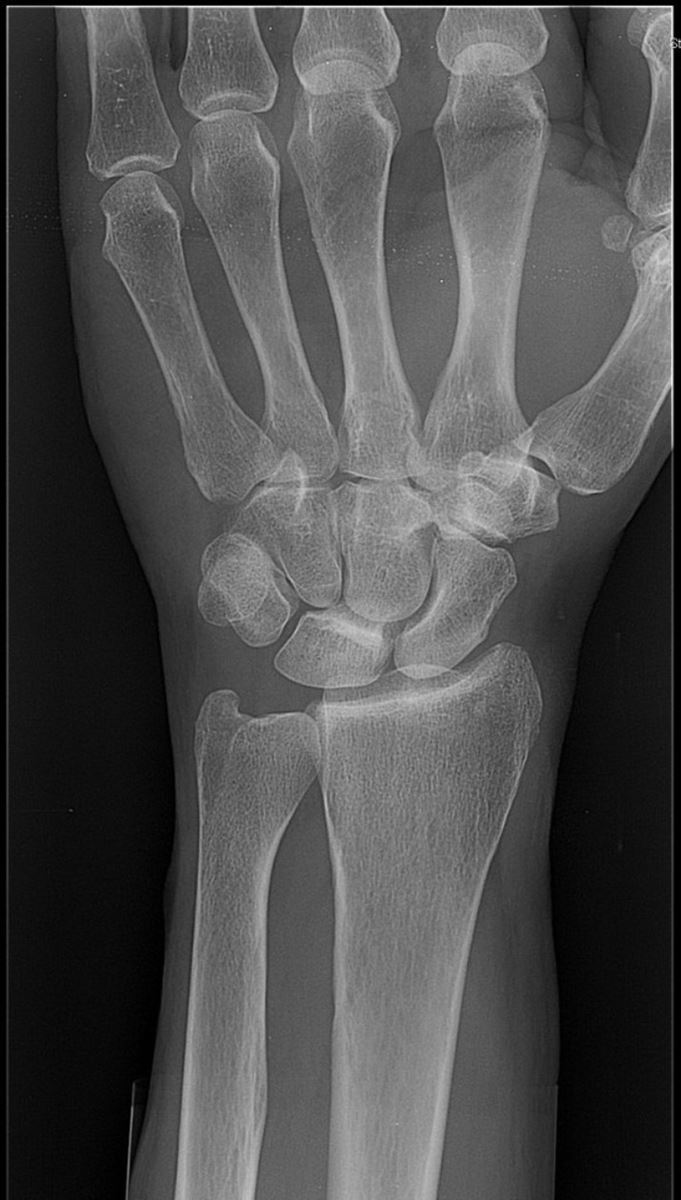

Gebroken linker pols

De meest voorkomende fractuur is de distale fractuur van de radius. Het is belangrijk dat de arts weet welk type fractuur u hebt. Het type bepaalt namelijk de behandeling.

- Bij onstabiele verplaatste fracturen is de stand van de pols vaak anders in vergelijking met de andere hand.